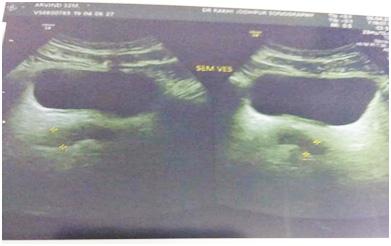

Ultrasound studies : Ultrasound showed cystic lesions in 17 patients and solid masses in three. Medial locations of a cystic retro-vesical mass were consistent with a prostatic utricle cyst (Fig 1) or abscess (Fig 2). Transrectal ultrasound was performed

additionally in eight patients to confirm the intraprostatic or extra-prostatic location of the cysts. Ultrasound revealed mixed echogenic masses in all the three patients with retro-vesical teratoma (Fig 3) which was difficult to differentiate from haematoma and four patients had cystic lesion contained hyperechoic material consistent with dermoid cyst but one letter on confirm on HPE was mullerian duct cyst with cystadenoma. A cystic extra-prostatic mass lateral to

the bladder neck was demonstrated on ultrasound for all seminal vesicle (Fig 4).

Fig 4 — USG images of seminal vesicle cyst Fig 1 — USG images showed prostatic cyst Fig 3 — Radiological images of Teratoma (case no 5)

Fig 2 — Radiological pictures of Epidermoid cyst (case no 3) and Last MRI picture showed b/l seminal vesicle cyst (case no 4)